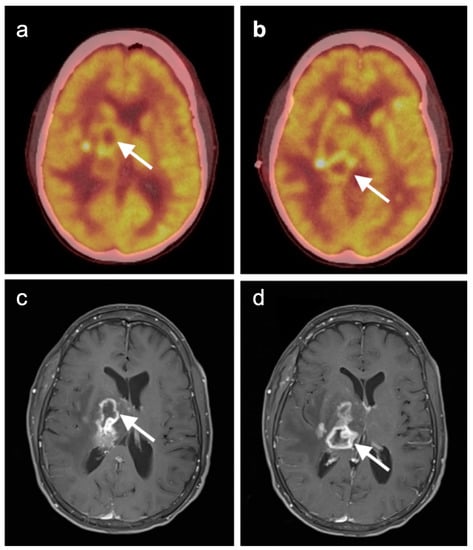

- Marcus, C.; Feizi, P.; Hogg, J.; Summerfield, H.; Castellani, R.; Sriwastava, S.; Marano, G.D. Imaging in Differentiating Cerebral Toxoplasmosis and Primary CNS Lymphoma With Special Focus on FDG PET/CT. AJR Am. J. Roentgenol. 2021, 216, 157–164. [Google Scholar] [CrossRef]

- Mukherjee, A.; Bal, C.; Tripathi, M.; Das, C.J.; Shamim, S.A. Cerebral Toxoplasmosis Masquerading CNS Lymphoma on FDG PET-CT in Post Renal Transplant Patient. Indian J. Nucl. Med. 2017, 32, 148–149. [Google Scholar] [CrossRef]